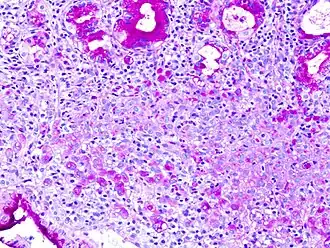

Periodic acid–Schiff (PAS) is a staining method used to detect polysaccharides (such as glycogen) and mucosubstances (such as glycoproteins, glycolipids and mucins) in tissues. The reaction of periodic acid oxidizes vicinal diols in these sugars, usually breaking up the bond between two adjacent carbons not involved in the glycosidic linkage or ring closure in the ring of monosaccharide units that are part of the long polysaccharides and creating a pair of aldehydes at the two free tips of each broken monosaccharide ring. The oxidation condition has to be sufficiently regulated so as to not further oxidize the aldehydes. These aldehydes then react with the Schiff reagent to give a purple-magenta color. A suitable basic stain is often used as a counterstain.

PAS staining is mainly used for staining structures containing a high proportion of carbohydrate macromolecules (glycogen, glycoprotein, proteoglycans), typically found in e.g. connective tissues, mucus, the glycocalyx, and basal laminae.

PAS staining can be used to assist in the diagnosis of several medical conditions:

- Adenocarcinomas, which often secrete neutral mucins.

- Fungal infection, the cell walls of fungi stain magenta; this only works on living fungi. In contrast, Grocott's methenamine silver stain (GMS) will stain both living and dead fungal organisms.